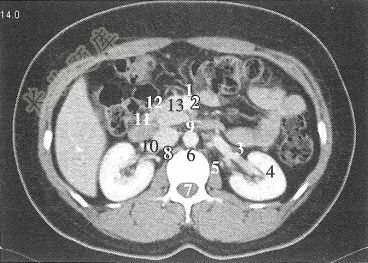

- 单项选择题经过肾门中份的横断层面,图中标注为4的器官是()

A、胃

B、肝

C、脾

D、左肾

E、右肾